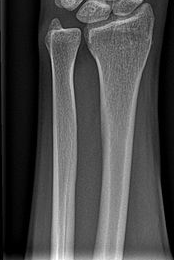

ПЕРЕЛОМ ЯКОЇ КІСТКИ І ЯКОЇ ЇЇ ЧАСТИНИ ВИ БАЧИТЕ НА РИСУНКУ?

варіанти відповідей

ДИСТАЛЬНОГО ДІАФІЗА

HUMERUS

ULNA

RADIUS

ПРОКСИМАЛЬНОГО ЕПІФІЗА

ДИСТАЛЬНОГО ЕПІФІЗА

ДІАФІЗА

МЕТАФІЗА

РОЗПІЗНАЙТЕ ДИСТАЛЬНИЙ ПРОМЕНЕВО-ЛІКТЬОВИЙ СУГЛОБ.